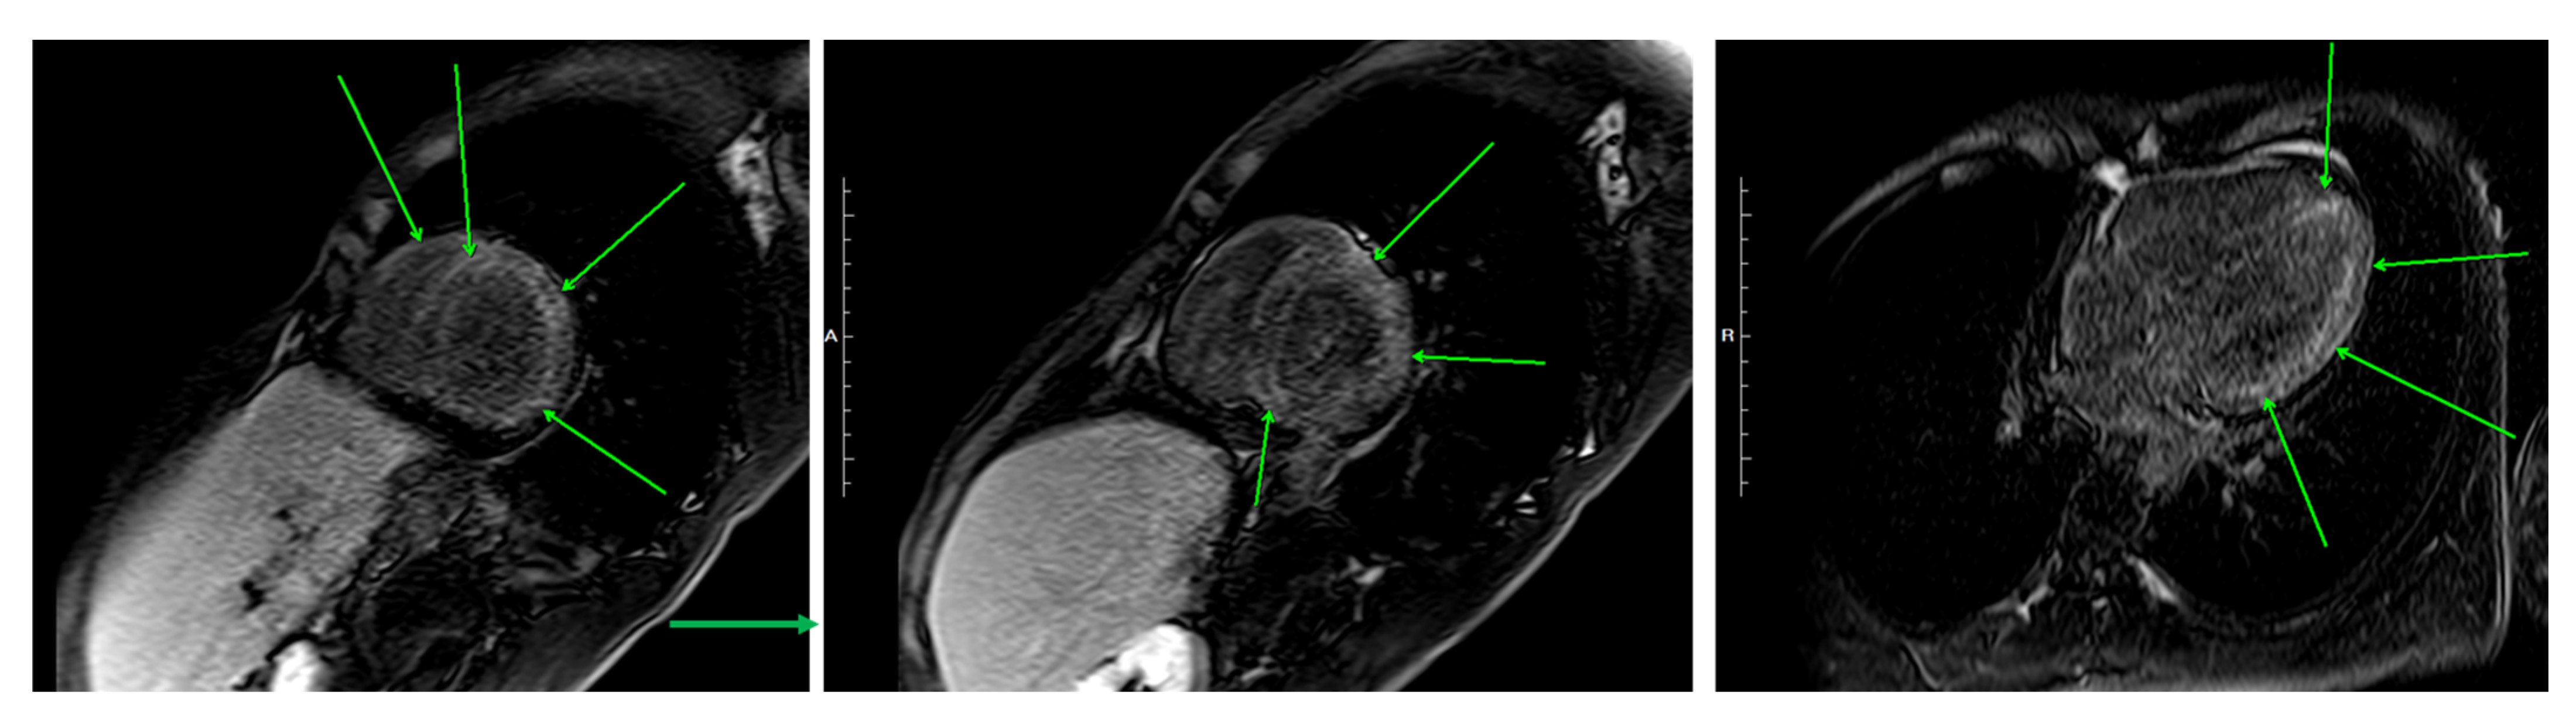

| This case, 2025 | 24, M | Japan | ANCA-negative EGPA | 13,060 | Sinus, asthma, lung, bone marrow | EF 47%, myocardial edema (Figure 2c) → EF 59% (Day 15)|biventricular subendocardial enhancement (Figure 5) | Mixed lymphohistiocytic + eosinophilic infiltrates, no necrosis | Steroids → mepo (300 mg) | Day 4—Initial therapy | Steroid-sparing, EF improvement, clinical improvement—remission at 19 months |